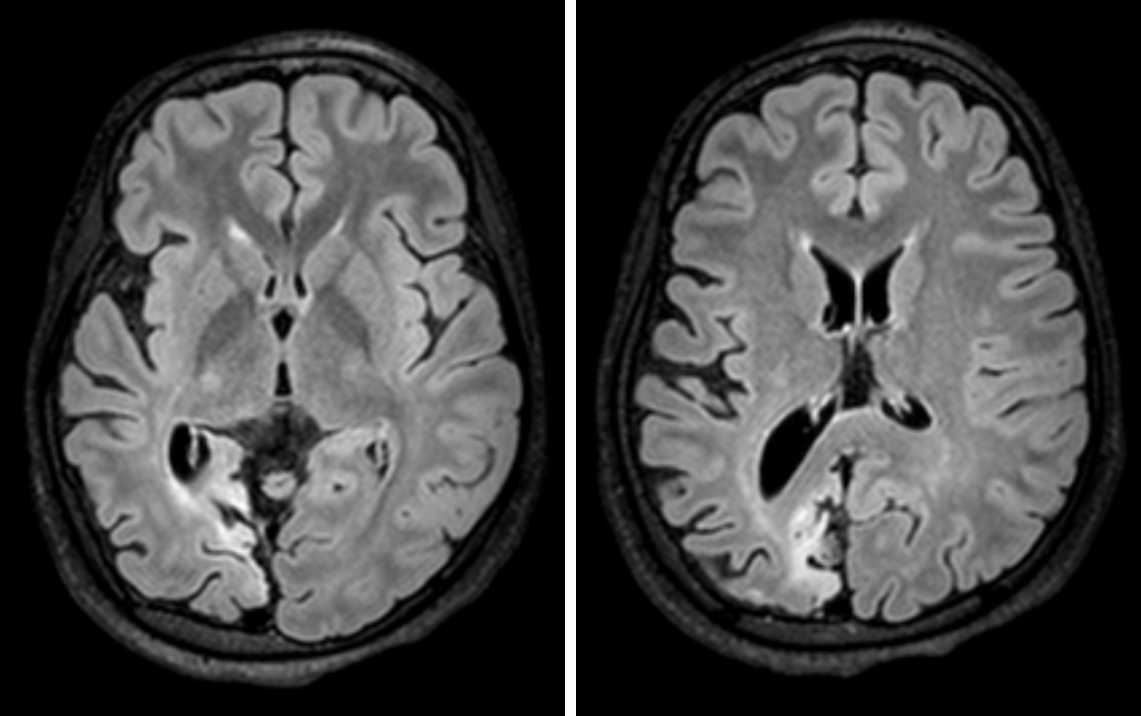

Question: A 6-year-old girl presents with involuntary jerking movements of her left leg followed by left arm since past 2 years. She had several episodes of this that would last for hours before stopping spontaneously and had no major response to levetiracetam. In the last 2 weeks, the patients mother has noted that she seems unaware during parts of these episodes and may have had twitching of the left side of her face. Electroencephalogram reveals right hemispheric spikes. A magnetic resonance image (MRI) of her brain is shown. Which of the following is the best treatment for this condition?

Explaination: This is a case of Rasmussen encephalitis. This commonly presents with focal motor seizures, which can last for extended periods. Eventually these seizures progress to involve contiguous structures and later generalized seizures as well. <br>Typically, epileptic discharges come from one hemisphere.<br>Imaging can show atrophy of the affected hemisphere, as is shown in the MRI. Positron emission tomography will show hypometabolism of the affected hemisphere.<br>Although some patients respond to IV immunoglobulin, the definitive treatment is hemispherectomy. Carbamazepine is good for partial-onset seizures and may be used in patients with Rasmussen encephalitis but will not adequately control seizures.